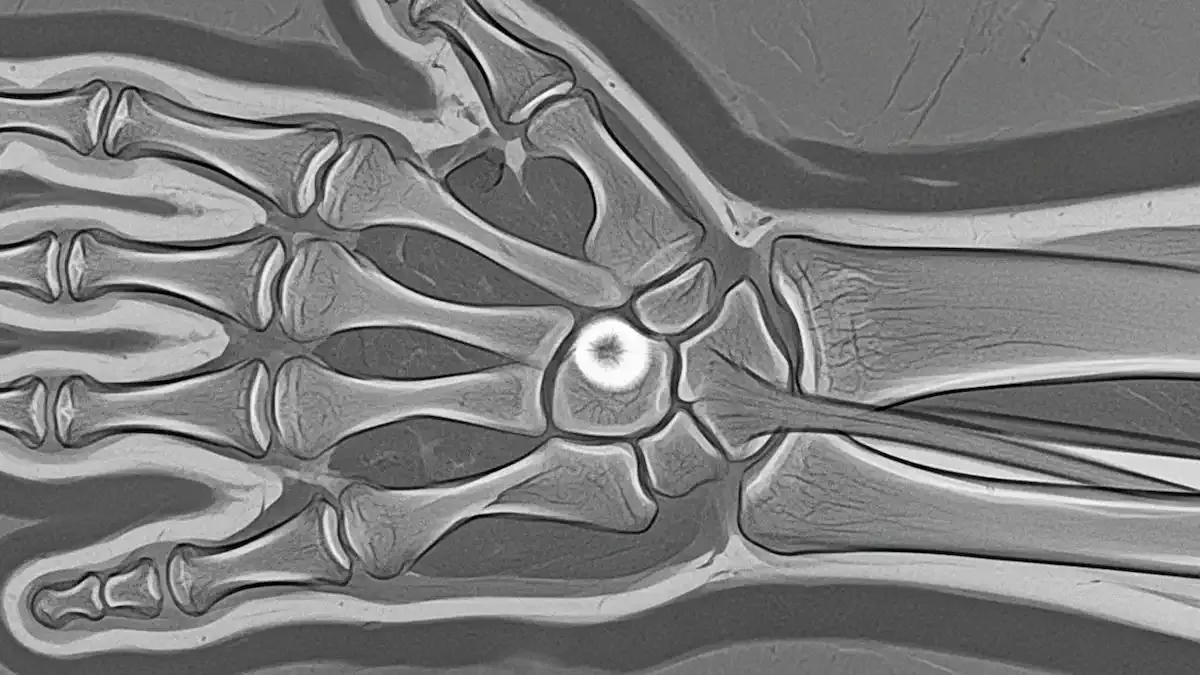

Como Saber Se Desloquei O Dedo Da Mão?

Lesões nos dedos são frequentes no consultório, principalmente após quedas, impactos ou atividades esportivas. Muitos dos meus pacientes ficam na dúvida: como saber se desloquei o dedo da mão? A luxação acontece quando os ossos da articulação saem...